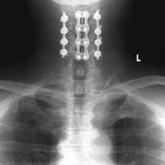

ArticleCombined Anterior-Posterior Decompression and Fusion for Cervical Spondylotic MyelopathyAuthor:Richard Bram, BSPublish date: March 9, 2017We conducted a study to evaluate the operative details, perioperative complications, and short-term outcomes associated with combined anterior-post...Read More